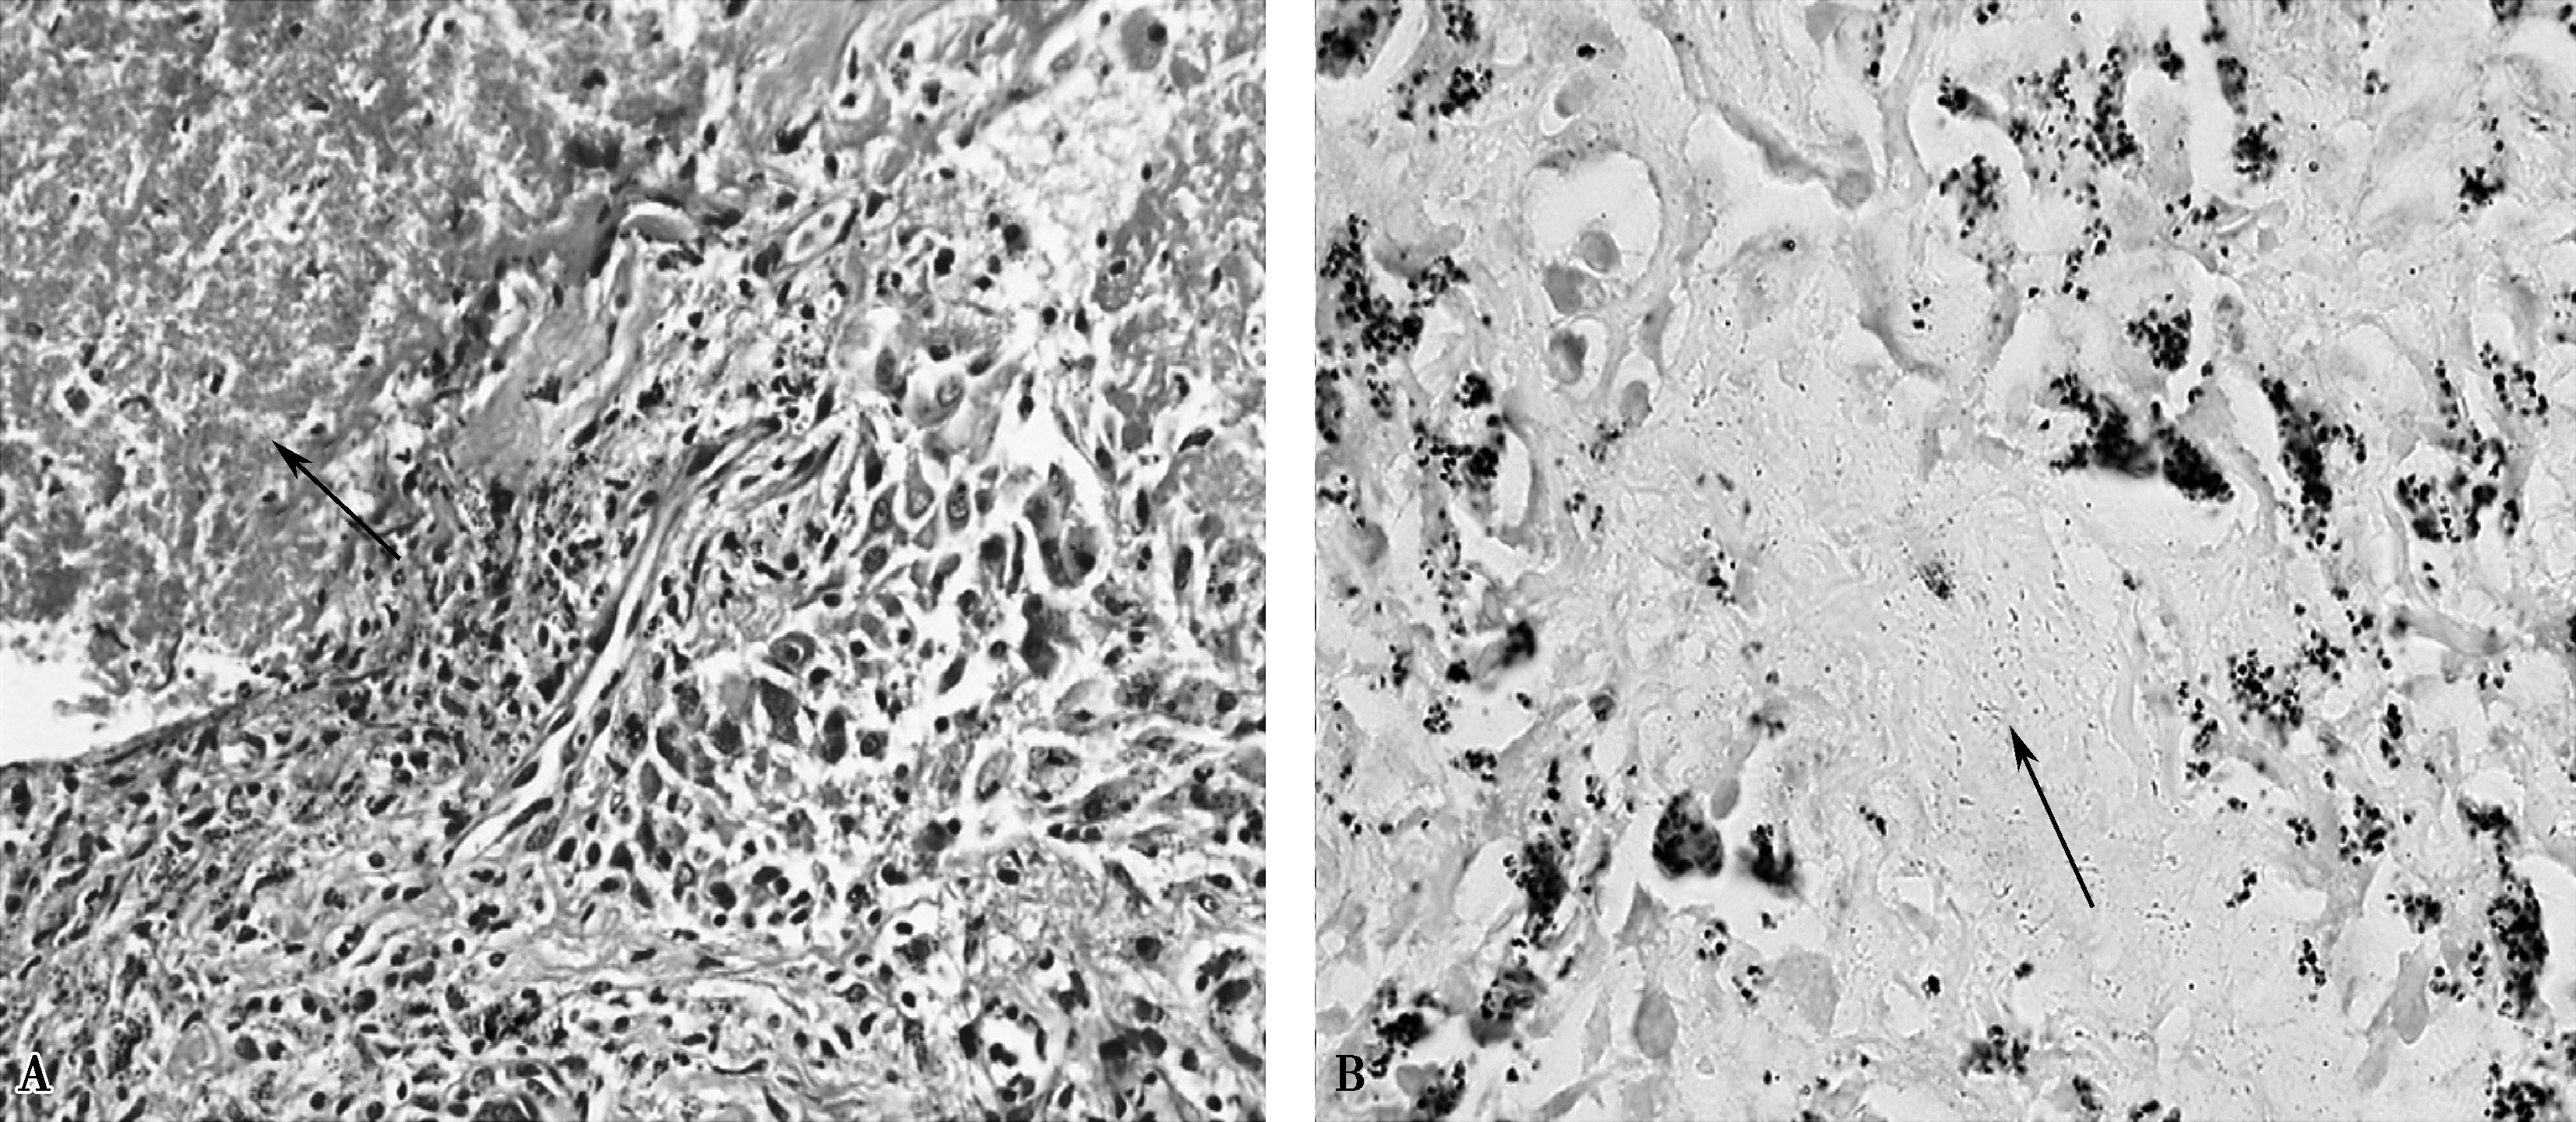

住院第28日复查心脏彩超示左心室血栓消失(图10-3),第29日CT引导下经皮肺穿刺活检病理结果回报:小灶型干酪样坏死组织,周围包裹上皮样细胞、多核巨细胞,伴间质、纤维组织增生,慢性炎性细胞浸润。抗酸染色找到抗酸杆菌(见文末彩图10-4)。

图10-4 肺活检病理

A.干酪样坏死(箭头所示);B.抗酸杆菌(箭头所示)